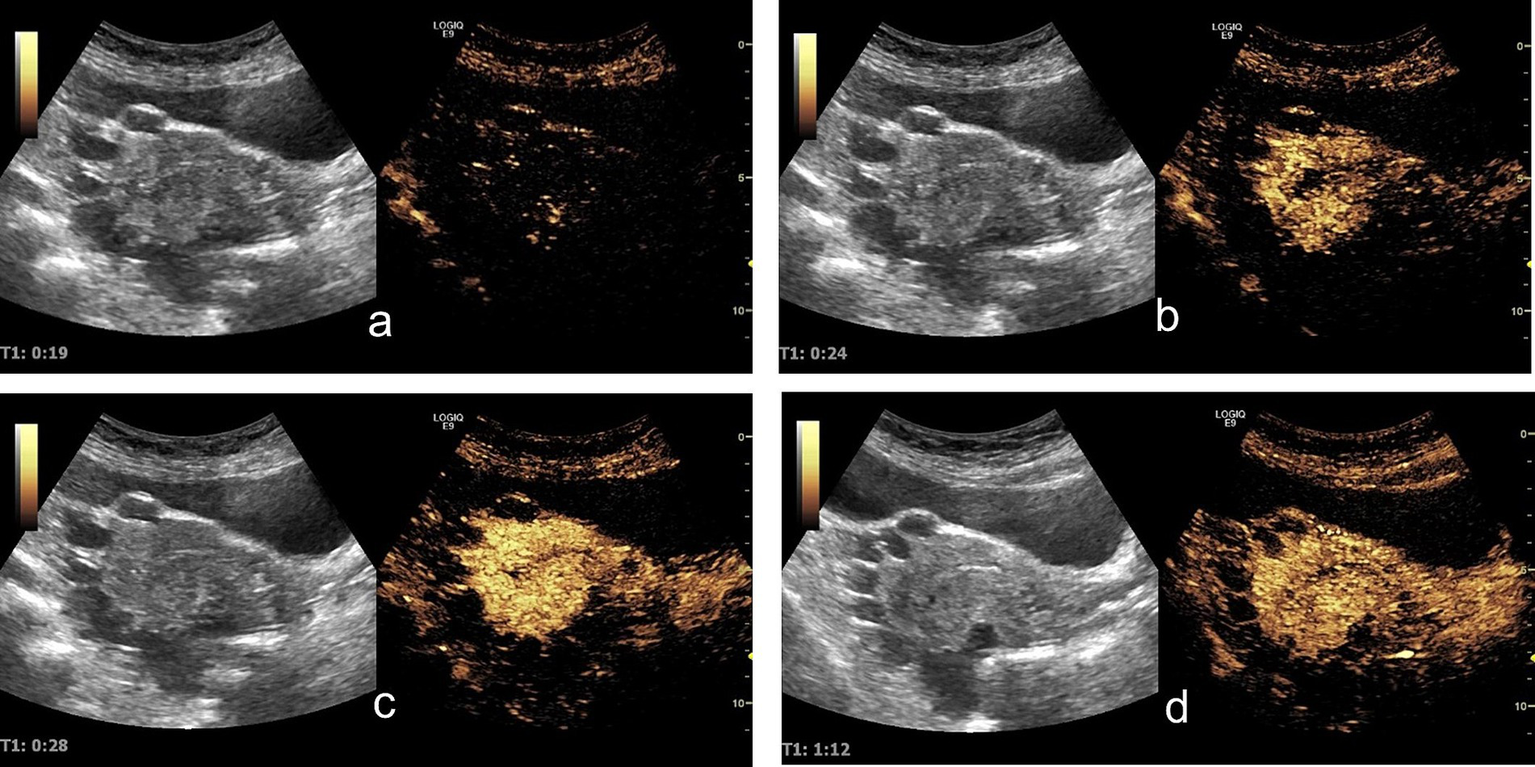

Contrast-enhanced ultrasound (CEUS) demonstrated sequential enhancement: myometrial enhancement began at 19 s (Figure 2a), with significant enhancement at 24 s (Figure 2b), followed by cyst wall and endometrial enhancement and marked myometrial enhancement (Figure 2c). The washout phase occurred at 72 s in the lesion capsule wall, endometrium, and myometrium (Figure 2d). The cysts displayed no internal enhancement throughout the examination.

Figure 2

Contrast-enhanced ultrasound findings: (a) At 19 s, the uterine myometrium begins to enhance. (b) At 24 s, the uterine myometrium shows significant enhancement, while no obvious enhancement is observed in the lesion walls or the endometrium. (c) At 28 s, the lesion walls and endometrium begin to enhance, with the uterine myometrium showing marked enhancement. (d) At 72 s: The contrast agent demonstrated a washout phase in the lesion capsule wall, endometrium, and myometrium.

The symptoms associated with endosalpingiosis can vary, with chronic pelvic pain being the most common complaint (3). Consistent with the literature, this case presented with chronic pelvic pain, although approximately 30% of patients are asymptomatic (3). Radiologically, the MRI findings in this case, including high signal intensity on T2-weighted images, low signal intensity on T1-weighted images, and mild enhancement of cyst walls on contrast-enhanced sequences, are consistent with the features of endosalpingiosis described in previous studies (6). However, the dynamic enhancement pattern observed on contrast-enhanced ultrasound (CEUS)—characterized by delayed enhancement of cyst walls with lower peak intensity compared to the myometrium—represents a novel finding not previously reported.